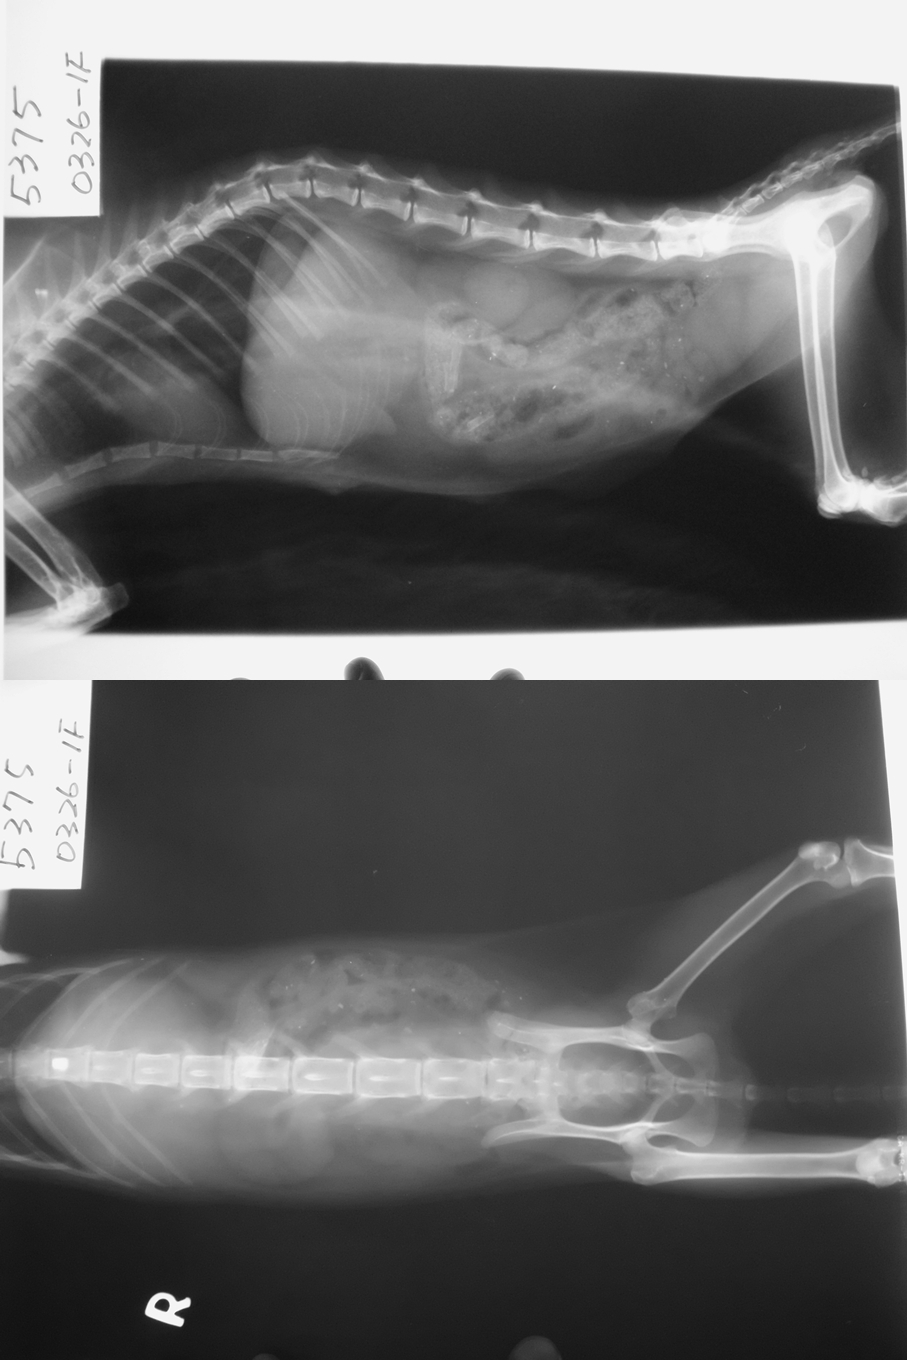

主題: 疑似車禍尾薦椎受傷且後驅癱瘓的貓 申請者姓名: 楊竣欽 花色: 申請日期: 2013-05-10 21:08:51 申請者部落格: 申請者臉書網址: 所在縣市/合作醫院: 高雄市/樂生動物醫院 治療費用: 17400元 需求人數: 19人 已結案 (2013-08-06 14:01:01) 報名人員: 邱小咪 x2(已付款)、Cindy Sung、Cindy Sung、philip x2(已付款)、alchow3、Mei-Yi Wu(已付款)、黑貓姐(已付款)、Anthony Weng(已付款)、euca(已付款)、Chen Ping(已付款)、胡嘟嘟(已付款)、chiawei x2(已付款)、Freessia Lin(已付款)、小七(已付款)、Tiffany Shen(已付款)、www.petsAholic.com - Ms. Richardson、Vicky Chang Shyr(已付款)、00(已付款)、呂嘎嘰(已付款)、KIKI(已付款)、 候補人員: 動物病情說明: 3/27早上7點多.因上班的途中.發現到一家保養場前的車子底下.躲著一隻白色小貓.於是就拿了早點分了一些要給小貓吃.正當要靠近時.發覺到小貓有點怪怪的.她好像不怕生..但又不太想讓我靠近的感覺.然後就慢慢的移動身體...我才發現到小貓的後腳根本沒有動..而且小貓動作的感覺好像很吃力.拖著走.可是小貓周圍都沒發現到血跡.之後.拍了照片.我就丟著食物在他旁邊..先行離開去上班.到公司在上網求助貴協會救援這隻小貓...然後有志工跟我連絡前來幫忙救援到此貓送到醫院檢查與治療.

2.X 光 300*2 = 600